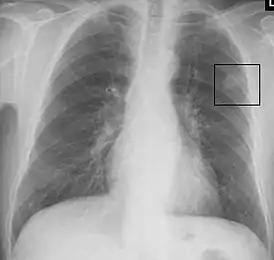

- Рак лёгкого

- Рентгенография, компьютерная томография, МРТ